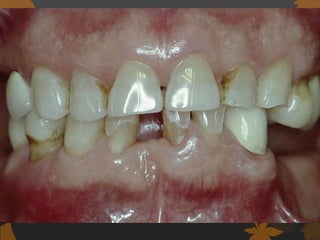

GINGIVITIS

 Diabetes is associated with increased

prevalence and severity of gingivitis.

 Children before puberty with poorly controlled

type 1 diabetes mellitus had a higher

incidence and severity of gingival

inflammation than controlled children.

Gusberti et al. 1983

 Cianciola et al.1982 Confirmed an increase in

gingivitis in type 1 diabetes mellitus children

after the age of 11

 poorly controlled diabetes mellitus

children has higher levels of gingival

inflammation regardless of plaque levels.

Firalti E. 1997